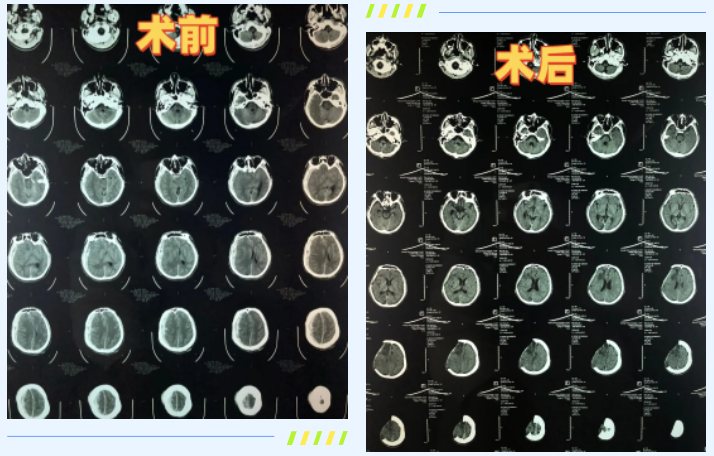

生死关头,北京燕化医院星城院区120急救中心火速奔赴现场。面对心跳呼吸骤停、生命体征完全消失的小何,急救人员没有片刻迟疑,立即展开持续高效的心肺复苏,同步配合呼吸机等专业设备实施精准施救。奇迹在不懈努力中降临——小何逐渐恢复微弱心跳。然而,后续CT检查结果更让人揪心:右侧广泛脑挫裂伤、创伤性硬膜下血肿、创伤性蛛网膜下腔出血、多发颅骨骨折、右侧脑室受压变形、中线向左移位,脑疝已然形成。如此复杂严重的复合型颅脑损伤,在临床救治中属于极高难度的危急重症,每一分钟的延误都可能导致不可逆转的脑损伤甚至死亡。

“时间就是生命,效率就是胜算!”120急救车一路疾驰,将小何送往北京燕化医院。医院早已开通危急重症绿色通道,收费处无需等候、直接衔接,医疗团队提前待命,全程零延误衔接救治流程。12时13分,小何转入急诊时仍处于深昏迷状态,自主呼吸微弱,双侧瞳孔不等大,右侧瞳孔散大固定,对光反射消失,生命体征极不稳定。医护人员立即启动最高级别紧急救治方案:呼吸机辅助呼吸、心电监护、药物升压、止血、降颅压等一系列操作有条不紊、精准落地。12时30分,小何突发抽搐,值班医生申利伟第一时间精准判断、下达医嘱,主管护师刘方雅毫秒级响应,迅速给予地西泮静脉推注,同时紧急联系神经外科会诊。经快速评估,小何被确诊为心肺复苏术后、闭合性颅脑损伤(特重型)、脑疝、创伤性硬膜下血肿、弥漫性轴索损伤,需即刻手术,否则随时可能因脑组织受压坏死而丧命。医护人员争分夺秒完成备皮、备血、导尿等术前准备,无缝衔接将其送往手术室。

当天下午1时许,神经外科程扬主任带领核心医疗团队全员到位,一场与死神的终极较量正式拉开序幕。脑疝状态下的开颅手术风险极高,手术视野受限,脑组织水肿严重,止血难度极大,且需精准把控去骨瓣减压的范围,既要解除颅内高压,又要最大程度保护正常脑组织功能。手术中,程扬主任团队凭借丰富的临床经验、精湛的显微操作技术,在高倍显微镜下小心翼翼清理碎裂的右侧部分头骨,精准清除硬膜下血肿,逐步解除脑组织移位,恢复脑组织正常解剖结构,同时逐一探查脑挫伤部位的隐匿出血点并彻底止血。手术室内,医护人员默契配合、精准操作,每一个动作都力求极致,每一个环节都严丝合缝,历经数小时高强度奋战,手术终获圆满成功,为小何保住了生命的核心希望。

术后,小何被立即转入ICU进行全方位监护治疗。ICU李耀森主任带领团队根据其病情特点,制定了个性化、精细化的救治方案,24小时不间断监护生命体征、调控颅内压、预防感染、营养支持。重型颅脑损伤患者的抢救黄金时间窗口极短,4分钟内大脑神经元就可能因缺血缺氧坏死,延误几分钟便会严重影响预后,而小何从现场急救、转运、术前准备到手术、术后监护,全程无缝衔接、及时高效,未出现任何环节延误。在ICU团队的精心照料下,小何创造了生命奇迹:术后第四天成功睁开眼睛,转出ICU的第二天下午便能磕巴着说话,元旦过后语言表达已完全流利,无明显障碍。在ICU的21天里,医护团队每天都会详细向守候在门口的家属告知患者病情变化与治疗进展,用专业与耐心缓解家属的焦虑,给予他们坚持的勇气与希望。李耀森主任表示,如此严重的特重型颅脑损伤能取得这样的恢复效果,在临床中极为少见,充分印证了医院危急重症救治流程的科学性与医疗团队的专业实力。